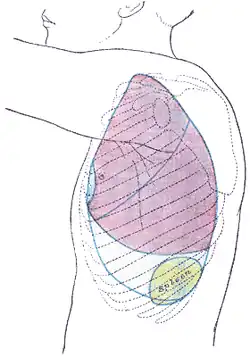

Splenomegaly is an enlargement of the spleen.[1] The spleen usually lies in the left upper quadrant (LUQ) of the human abdomen. Splenomegaly is one of the four cardinal signs of hypersplenism which include: some reduction in number of circulating blood cells affecting granulocytes, erythrocytes or platelets in any combination; a compensatory proliferative response in the bone marrow; and the potential for correction of these abnormalities by splenectomy. Splenomegaly is usually associated with increased workload (such as in hemolytic anemias), which suggests that it is a response to hyperfunction. It is therefore not surprising that splenomegaly is associated with any disease process that involves abnormal red blood cells being destroyed in the spleen. Other common causes include congestion due to portal hypertension and infiltration by leukemias and lymphomas. Thus, the finding of an enlarged spleen, along with caput medusae, is an important sign of portal hypertension.[2]

Signs of splenomegaly may include a palpable left upper quadrant abdominal mass or splenic rub. It can be detected on physical examination by using Castell's sign, Traube's space percussion or Nixon's sign, but an ultrasound can be used to confirm diagnosis. In patients where the likelihood of splenomegaly is high, the physical exam is not sufficiently sensitive to detect it; abdominal imaging is indicated in such patients.[11]